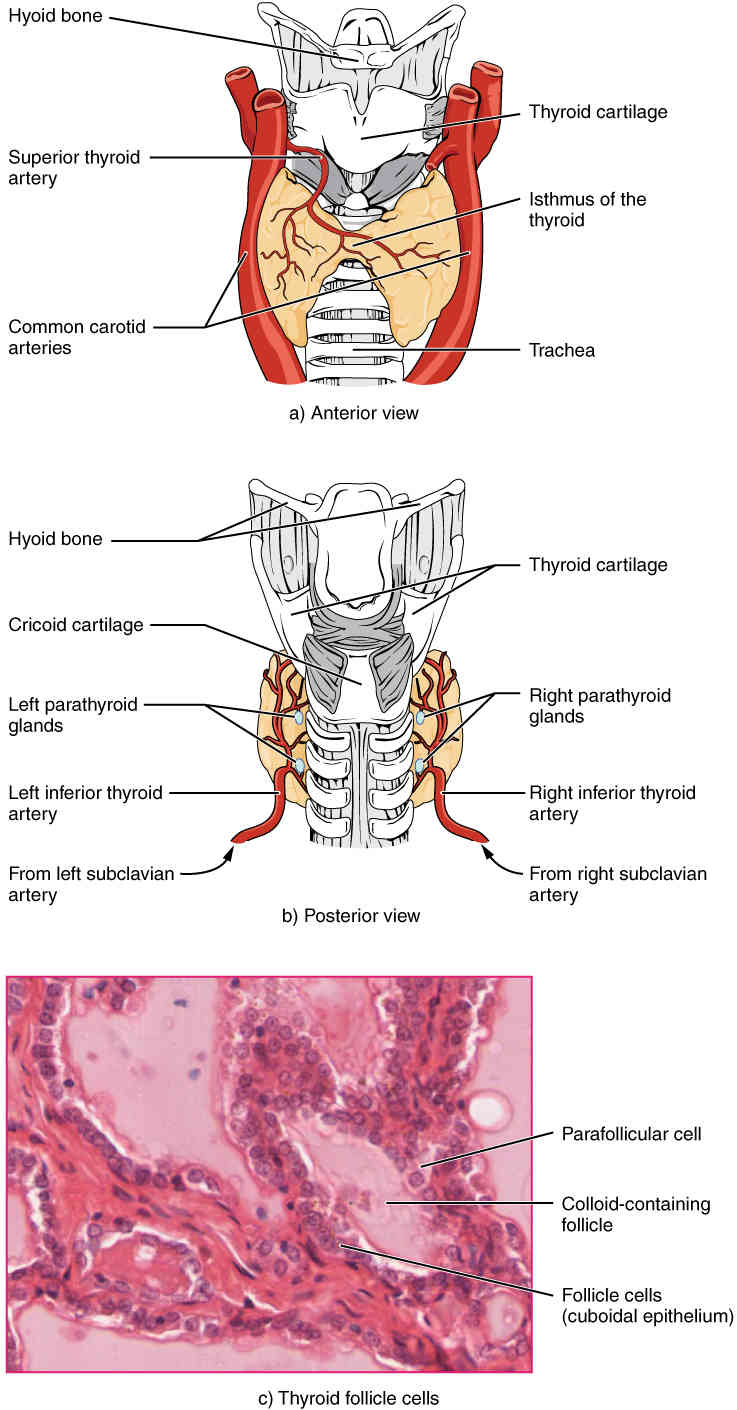

This page is under construction. For now, it is just a resource of the images found in the OpenStax Anatomy and Physiology Handbook. It wil slowly change into a revision tool. Each slide has a number. Use this to refer to the slide. When completed, it will have an unlabelled section, with labelled slides in parallel. On the unlabelled slides, write your answer and use the labelled slide to assess yourself. Keep track by also noting the number on each slide. Improvement at each attempt is important, more so than full marks on a first attempt.